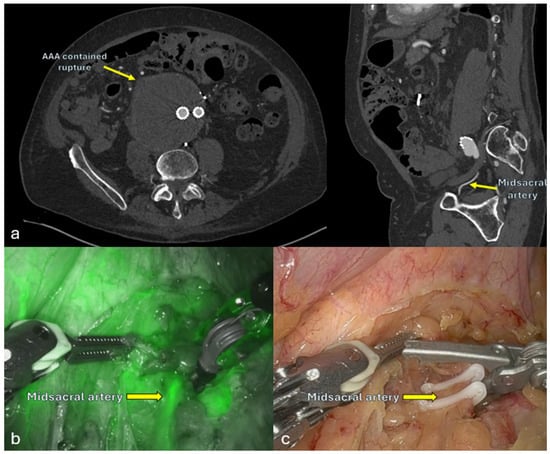

3.4. Type II Endoleak Management